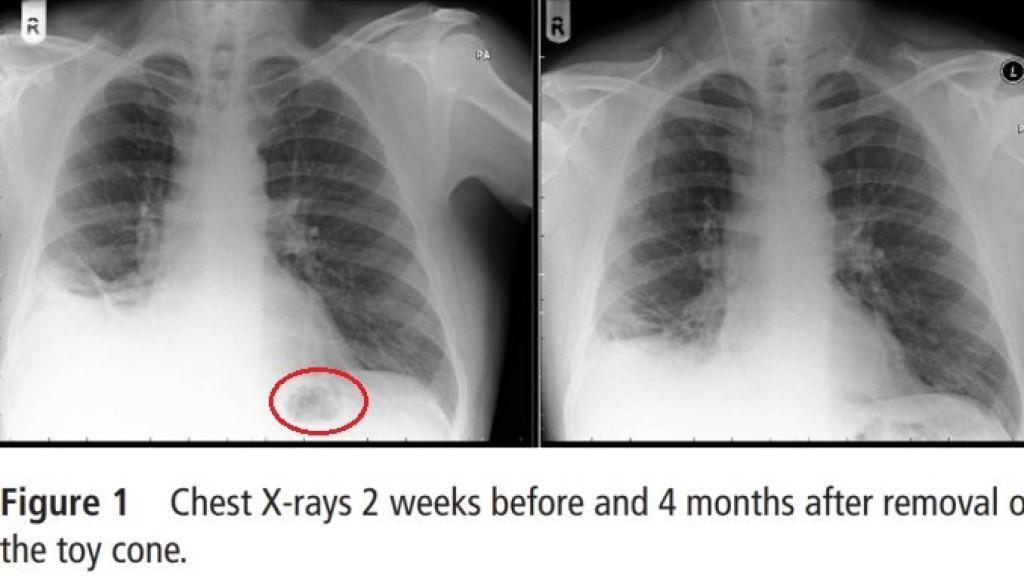

Así, con el objetivo de encontrar una explicación a su extraña dolencia, los médicos decidieron radiografiar de nuevo sus pulmones y hallaron una preocupante mancha en uno de ellos. La sombra que aparecía en las placas había reducido significativamente el volumen de su pulmón izquierdo. El diagnóstico, a priori, estaba claro: tenía un tumor maligno. En concreto, un carcinoma broncogénico.

Los pulmones del paciente antes y después de que le fuese extraído el cono de plástico.

Cuatro meses después de eliminar el objeto, la persistente tos que sufría se había aclarado y la sombra en su pulmón había desaparecido. "Sus síntomas mejoraron notablemente y finalmente encontró el cono de tráfico de Playmobil perdido en el último lugar en el que habría mirado", finalizan los facultativos.